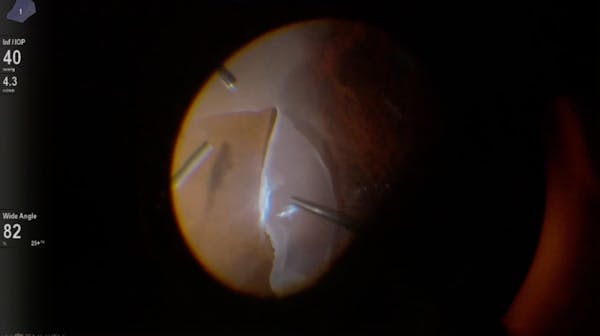

Slawomir Cisiecki, MD

Andre Gomes, MD